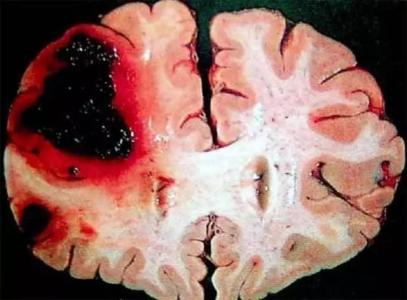

腦出血是指非外傷性腦實質內血管破裂引起的出血,占全部腦卒中的20%~30%,急性期病死率為30%~40%。發(fā)生的原因主要與腦血管的病變有關,即與高血脂、糖尿病、高血壓、血管的老化、吸煙等密切相關。腦出血的患者往往由于情緒激動、費勁用力時突然發(fā)病,早期死亡率很高,幸存者中多數(shù)留有不同程度的運動障礙、認知障礙、言語吞咽障礙等后遺癥。

腦度溢血發(fā)病主要原因是長時間高血壓、動脈硬化。絕大多數(shù)病人發(fā)病那時血壓明顯升高問,導致血管破裂,引起腦出血。

絕大多數(shù)是高血壓病伴發(fā)的腦小動脈病變在血壓驟升時破裂所致,稱為高血壓性腦出血。